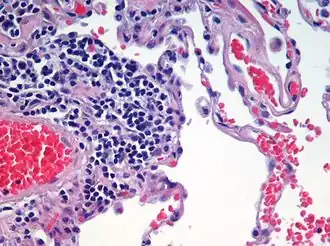

| Advanced centrilobular emphysema showing total lobule involvement on the left side | |

Centrilobular

Centrilobular emphysema, also called centriacinar emphysema, affects the centre of a pulmonary lobule (centrilobular) in the lung, the area around the terminal bronchiole and the first respiratory bronchiole, and can be seen on imaging as an area around the tip of the visible pulmonary artery. Centrilobular emphysema is the most common type usually associated with smoking, and with chronic bronchitis.[17] The disease progresses from the centrilobular portion, leaving the lung parenchyma in the surrounding (perilobular) region preserved.[23] Usually the upper lobes of the lungs are affected.[17]